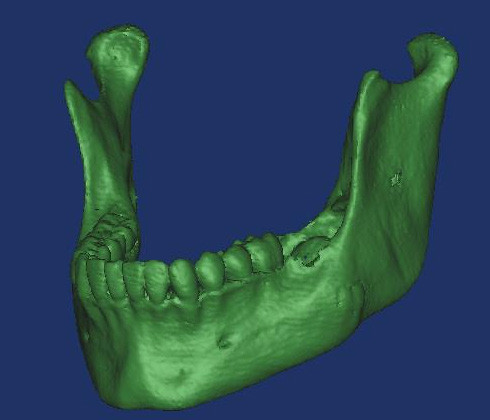

En caso de que el médico cirujano o institución solicitante posea alguna capacidad de impresión 3D, nosotros ofrecemos el servicio de generación de los archivos en formato STL (stereolithography) necesarios para imprimir una pieza ósea en una impresora 3D.

En caso de que el médico cirujano o institución solicitante posea alguna capacidad de impresión 3D, nosotros podemos ofrecer el servicio de generación de los archivos con formato STL (stereolithography) necesarios para imprimir una pieza ósea en una impresora 3D. Los archivos STL también son usados para generar modelos computacionales de las piezas óseas tanto para visualización como para simulación computacional.